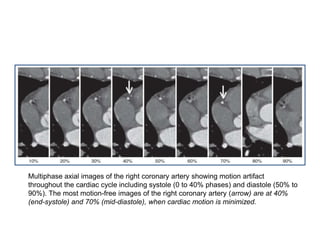

Multiphase axial images of the right coronary artery showing motion artifact

throughout the cardiac cycle including systole (0 to 40% phases) and diastole (50% to

90%). The most motion-free images of the right coronary artery (arrow) are at 40%

(end-systole) and 70% (mid-diastole), when cardiac motion is minimized.